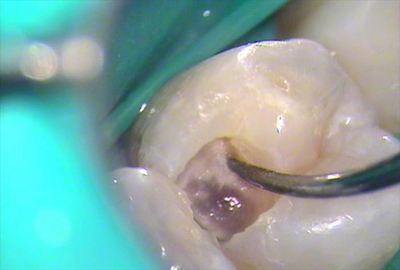

顕微鏡下で慎重に切削していきます。

第一小臼歯の過去のレジンを取り除いていきましたら、内部の軟化象牙質が見えてきました